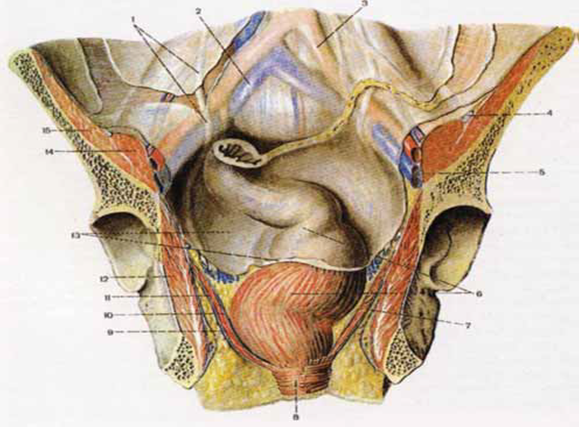

Анатомия малого таза: детальные схемы и изображения

Раздел: Образы вокруг